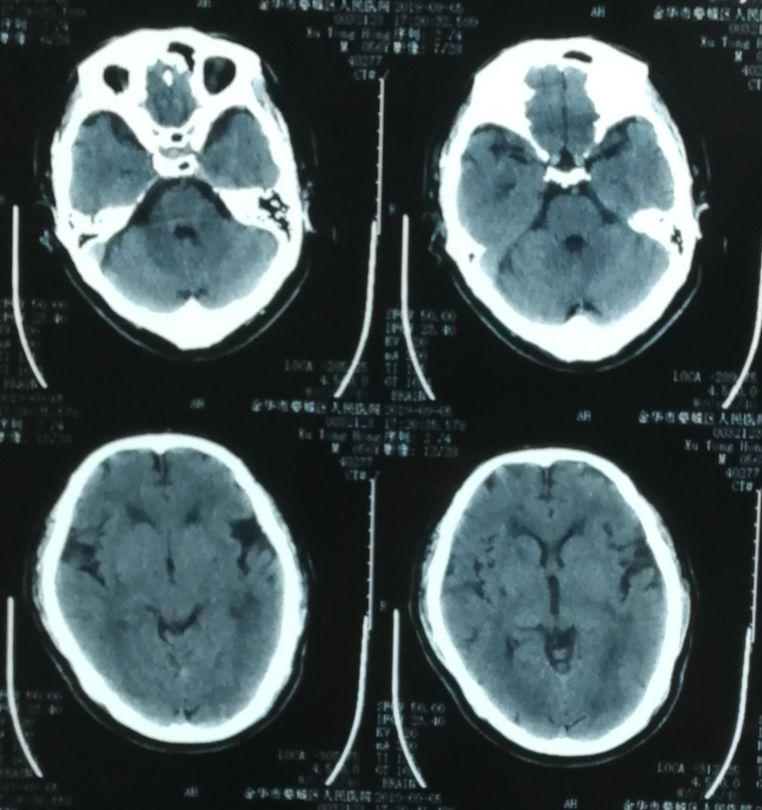

当地医院头CT检查(2019-9-9)(图1 )

图1